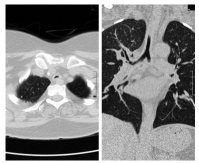

In January 2017, she presented with two- week history of worsening of shortness of breath, wheeze and stridor. Further evaluation showed interval increase in circumferential thickening of trachea and bilateral main stem and lobar bronchi on HRCT of the chest and neck. However, repeat ANCA was negative for both proteinase 3 and MPO by line immunoassay and by indirect immunofluorescence for cytoplasmic and peri-nuclear ANCA. After initial treatment with broad-spectrum antibiotics and increased steroid dose, she had a marginal improvement. Considering this as a disease relapse, she was given rituximab 2 g two weeks apart. At subsequent follow-ups, the patient was doing well with just oral prednisolone 5 mg daily. At fourth month follow-up, HRCT of the chest with neck cuts was repeated and it showed reduction in wall thickening as compared to the previous scans (Figure 2). This time, the patient was given early rituximab 500 mg maintenance therapy and discharged on same dose of oral prednisolone and cotrimoxazole.